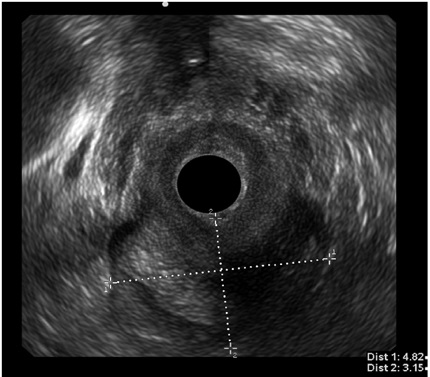

Por otro lado, en el grupo masculino con estudio por incontinencia, el diagnóstico en todos fue cambios por atrofia del aparato esfinteriano, que pudo verse en cualquiera de las localizaciones del canal anal y que se evidenció como engrosamiento de los músculos en general y cambios difusos de la ecogenicidad de los mismos, sin posibilidad de determinar el borde que los delimita. Se encontró fístula perianal en 16 pacientes (11,8%); la principal forma de presentación de las fístulas fue transesfintérica (37,5%), seguida por las interesfintéricas y anovaginales (figuras 3 y 4). Doce pacientes presentaron absceso perianal (8,8%); de estos, el 83% correspondió a abscesos submucosos o isquiorrectales (figura 5).

Los demás diagnósticos finales se presentan en la tabla 4. Es de resaltar que se pudo determinar en el grupo diagnosticado como neoplasia benigna de recto, la posibilidad de resección endoscópica en lesiones que tenían planeadas cirugías más invasivas (figura 6 y 7), así como la posibilidad de determinar la recuperación del aparato esfinteriano en 3 pacientes en seguimiento por cáncer de canal anal después de manejo por parte de oncología. En 2 pacientes de los diagnosticados con neoplasia maligna de recto se identificó lesión menor a T2 y N0 según las clasificación de TNM (figura 8), considerándose lesiones tempranas; en el otro 88,8% se encontraron lesiones avanzadas (figura 9 y 10). También se anota que, dentro de la categoría otros, están con orden de frecuencia de mayor a menor endometriosis o endometrioma, enterocele, fisura anal, várices rectales y un caso de cáncer de colon sigmoides.